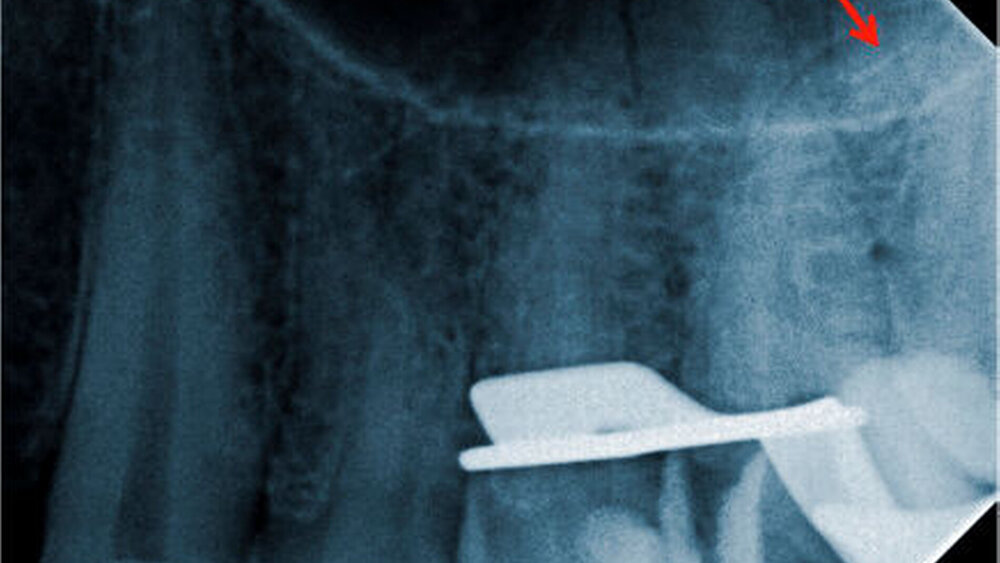

Im Zuge der maschinellen Aufbereitung frakturierte dem Behandler die S1-Feile des ProTaper-Universal-Systems (Dentsply Maillefer, Ballaigues, Schweiz). Zur Bestimmung der Länge und der Lage des im Wurzelkanal verbliebenen Bruchstücks wurde ein Röntgenbild angefertigt. Die exzentrische Aufnahme des Zahnes zeigt, dass ein etwa zwei bis drei Millimeter langes Fragment im apikalen Wurzeldrittel hinter der starken Krümmung klemmt (Abbildung 2). Der Patient wurde über diesen Zwischenfall aufgeklärt. Zusammen mit dem Patienten wurde das weitere Vorgehen diskutiert.

Die Chancen auf die vollständige Entfernung des Bruchstücks wurden als eher gering eingeschätzt. Dies liegt zum einen an der tiefen Lage des Fragments im apikalen Wurzeldrittel hinter einer stark ausgeprägten Krümmung, zum anderen wirkt sich die geringe Länge des Fragments nachteilig auf den Entfernungsversuch aus [Hülsmann and Schinkel, 1999; Arnold, 2013]. Ein Belassen des Fragments käme infrage, zumal es sich in diesem Fall um ein nicht-infiziertes Wurzelkanalsystem handelte.